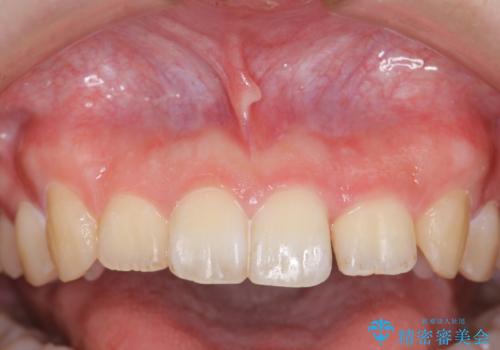

マススピース矯正を始める前に、部分ワイヤー矯正を行うことで治療の短期間化・良好な仕上がりを達成することができました。

- ねじれの目立つ前歯を改善したいと、矯正治療を希望され来院されました。

上顎前歯のねじれはマウスピースで治りづらいため、マウスピース矯正の治療期間の長期化をきたしやすい歯列不正です。